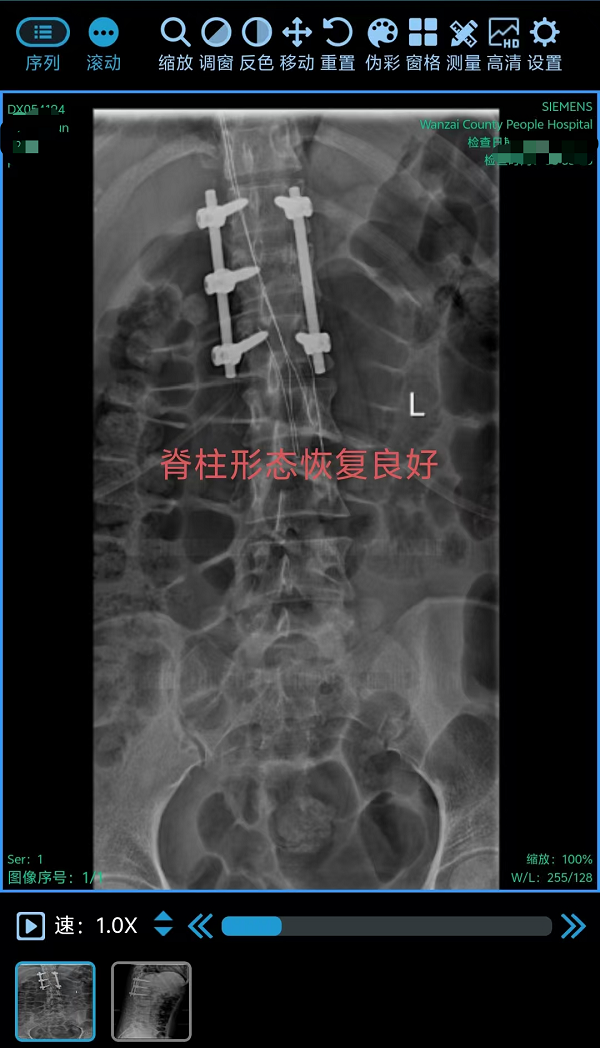

在丁晔副主任医师带领下,团队联合彭晴医师等医护人员,成功完成3台分属颈、胸、腰椎三大区域的高难度脊柱外科手术,病种涵盖退行性病变与创伤性骨折,融合微创内镜与经典开放技术,彰显科室综合诊疗实力。

3. 为胸椎爆裂性骨折患者施后路切开复位、微创减压内固定术(四级手术),胸椎爆裂性骨折常因高能量损伤导致,骨折块可能突入椎管压迫脊髓,致残风险高。丁晔副主任医师团队采用微创理念进行减压,并完成了有效的复位与坚强的内固定,既解除了对神经的压迫,又最大程度地减少了手术创伤,为患者争取了最佳的神经功能恢复条件。

三台手术均顺利完成,患者术后恢复良好,标志着我院脊柱疾病微创化、精准化治疗迈上新台阶。